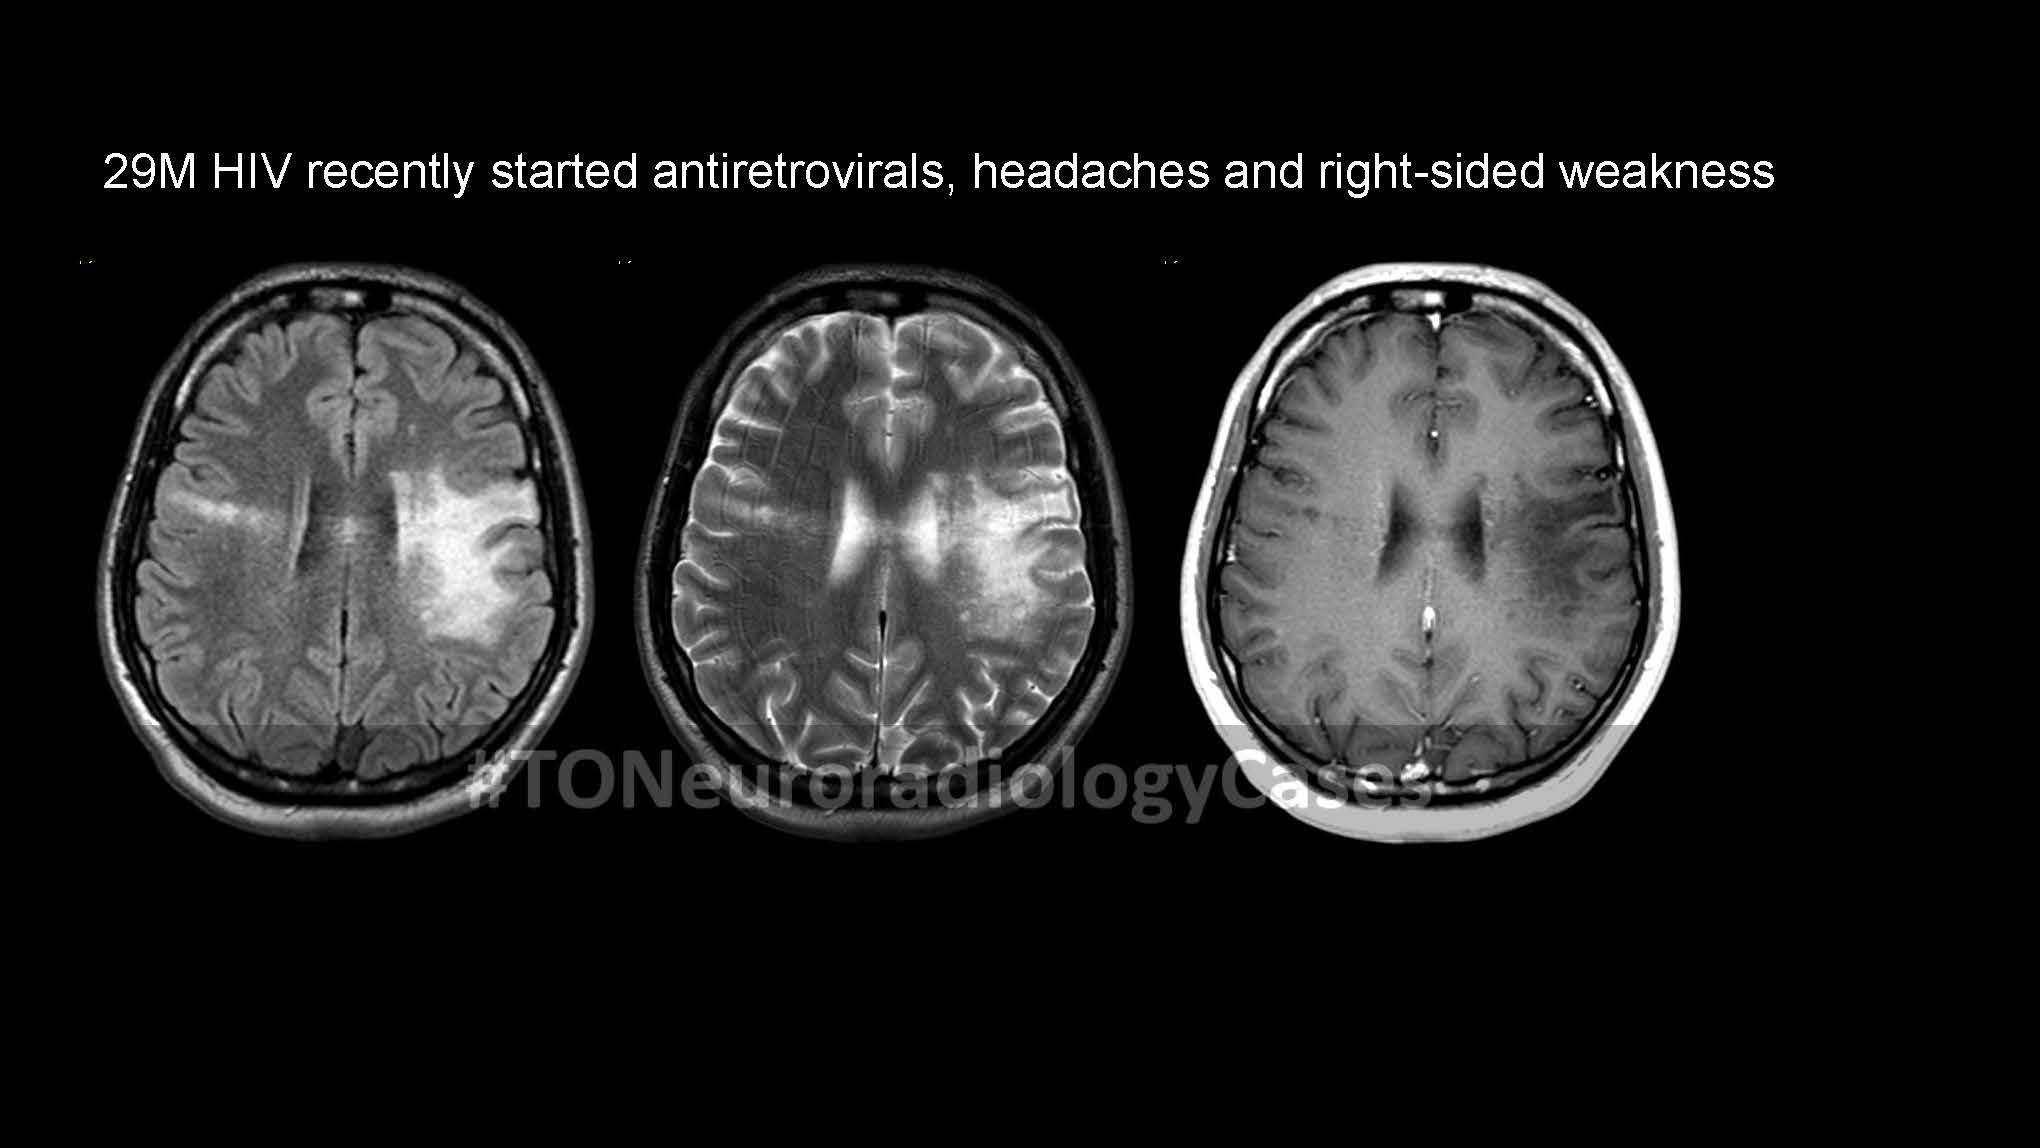

DR. AMY CHEN’S

Neuroradiology Case of the Week

@ Toronto Radiology

Over the past few years, I’ve had the pleasure of curating a “Case of the Week” contest with contributions from radiologists across the city, designed to challenge and engage our neuroradiology fellows at the University of Toronto. This collection showcases a range of neuroradiology cases from our city and have been a fun part of our fellow’s educational experience. I am excited to share this resource with a wider audience, now featured on our Toronto Radiology departmental website.